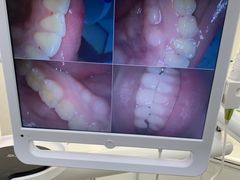

• 牙博士口腔品牌连锁(杨浦店)

• -牙博士口腔品牌连锁(杨浦店)

匿名用户 | 21-03-28